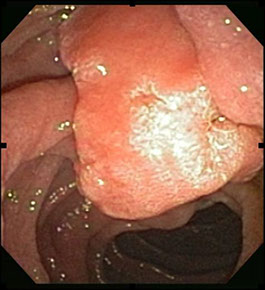

Cáncer de las Vías Biliares

El cáncer de vías biliares es una enfermedad poco frecuente por la que se forman células malignas (cancerosas) en los conductos biliares. Una red de tubos, que se llaman conductos, conectan el hígado, la vesícula biliar y el intestino delgado. El cáncer devías biliares también se llama colangiocarcinoma.

Es una forma poco frecuente, aunque agresiva, de cáncer.

Los síntomas incluyen el color amarillento de la piel y los ojos (ictericia), comezón en la piel y heces de color blanco.